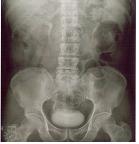

경정맥신우조영술은 조영제를 정맥에 투여한 다음 몇 차례에 걸쳐 단순방사선촬영(X-ray)을 하는 검사로, 신장 기능에 문제가 없는 경우 사용합니다. 이 검사로는 조영제가 신장에서 신우나 요관으로 배설되는 상황, 종양의 유무 등의 이상을 확인할 수 있습니다.

[ 경정맥신우조영술 ]